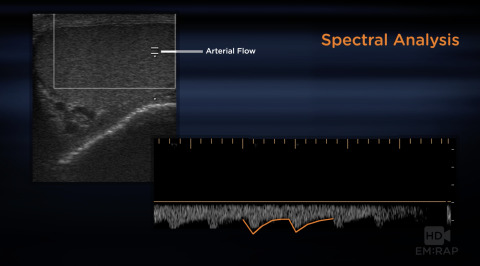

Ultrasound of Testicular Torsion

An overview of the ultrasound findings in testicular torsion, grayscale and spectral analysis, and ultrasound guided manual detorsion. Corresponds to EMRAP September 2016. Presented by Dr. Robert Jones, Ultrasound Director at MetroHealth Medical Center.